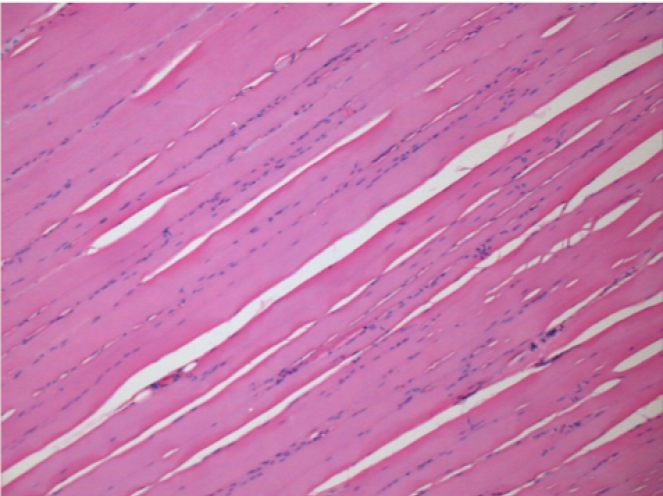

Через 3 місяці (90 днів) після ін'єкції Ендопіл 0,1 мл в правий претибіальний м'яз.